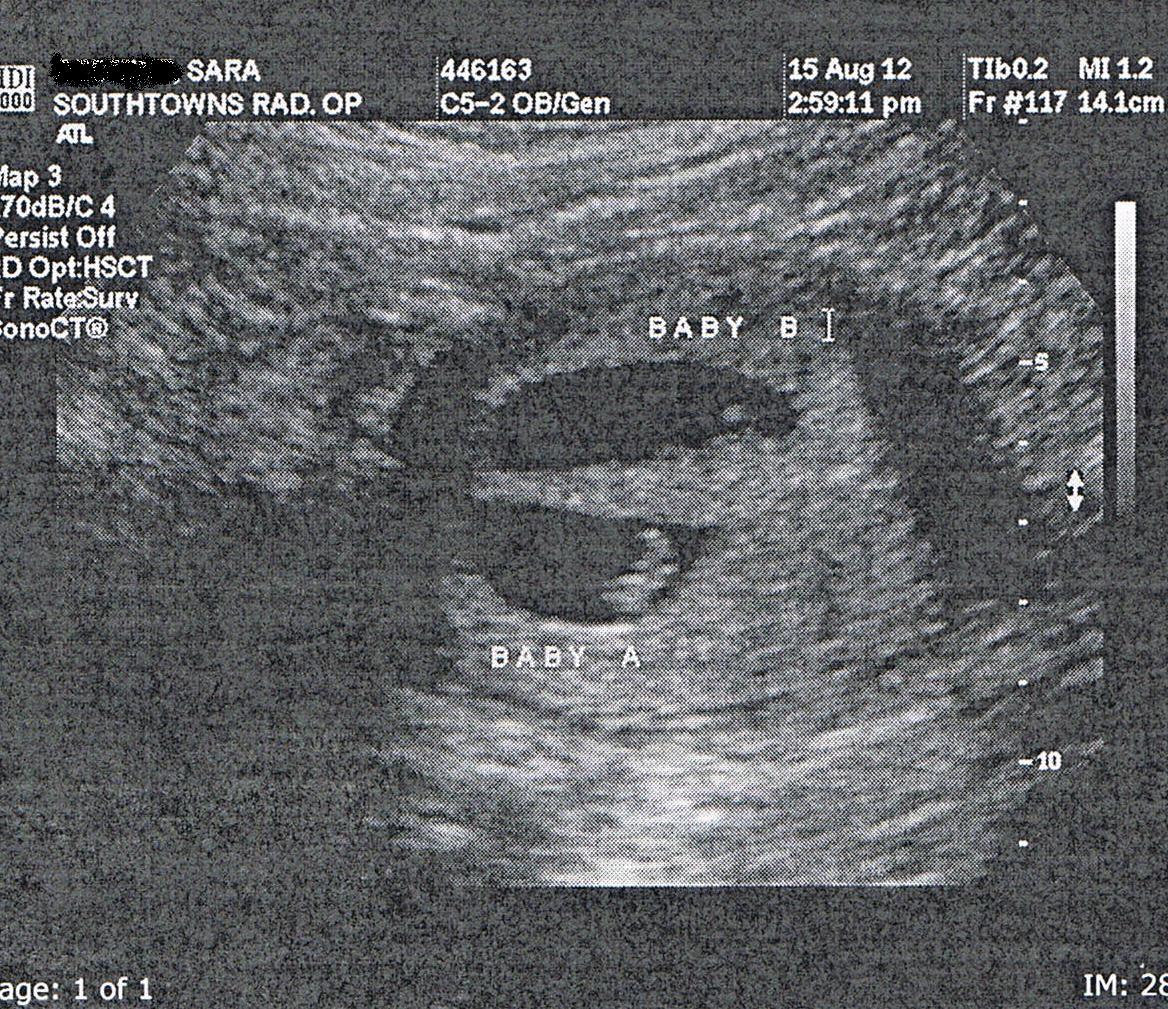

We dragged the poor kids out of bed and to the hospital with us, and Ed’s brother and fiance met us there to keep an eye on them. I had blood work, a sonogram and an internal exam, and everything was normal–we had 2 heart beats, closed sacs and a closed cervix. By this time, I wasn’t actively bleeding anymore. Everything was chalked up to a fluke. Could have been a blood vessel that broke, could have been anything really. They had no idea. So I was sent home with instructions to take it easy for a few days, no lifting the kids, no work in general, just basically bed rest. So I stayed in bed and on the couch for the rest of the day, and today I am down in my office, but am doing my best to just sit here, and not go upstairs and do the dishes and clean up the kitchen (I swear, I take one day off and the house has EXPLODED), and take care of the 5 loads of laundry we have.

It was really cool to see the babies again. Where they seemed so far away from each other on my initial sonogram, they are one right next to the other now, head to head, just hanging out snug as bugs. We didn’t get to keep a picture, ER and all (plus, their machine was hoopty and OLD) but now I am really looking forward to my high resolution scan next week.